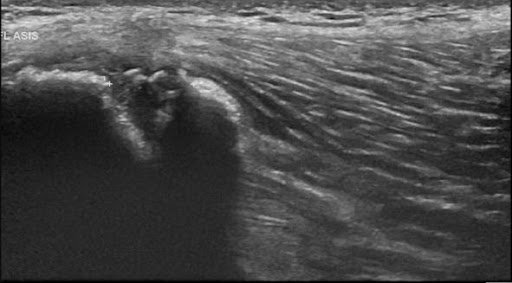

The below X-ray (2) and ultrasound images are from a young teen footballer with an acute, painful ‘pop’ over the high left lateral hip on landing from a jump.

He struggled to bear weight and retired. Examination revealed him unable to single leg squat, Tensor Fascia Lata loading and oblique crunches were sore; exquisitely tender with swelling over 8cm of the iliac crest to the anterior superior iliac spine.

Figure 8 and 9 revealed avulsion of the iliac crest apophysis – rare!!

Figure 9 – Ultrasound iliac crest